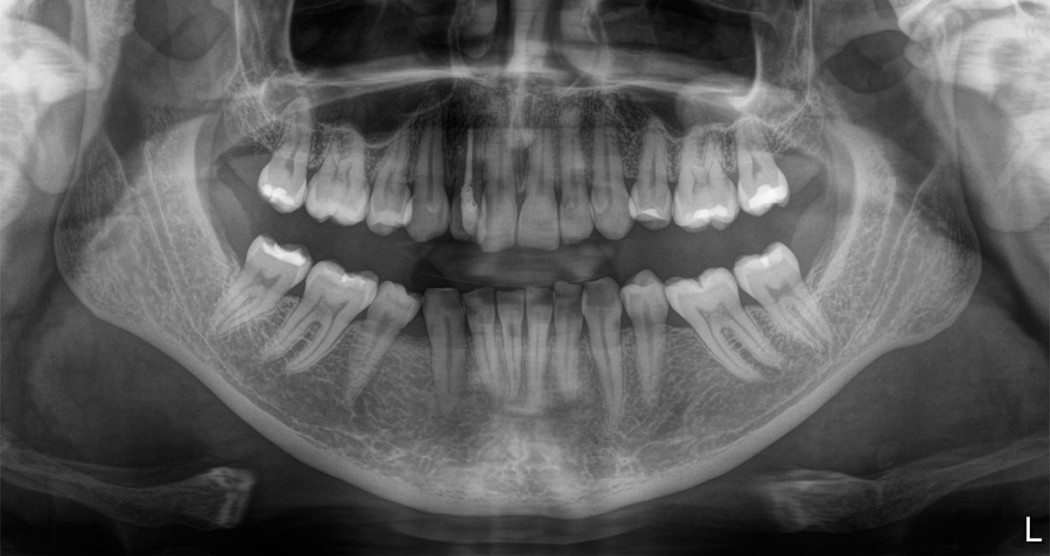

La imagen de rayos X muestra a un paciente (hombre, 59 años) con los siguientes hallazgos: osteítis periapical extensa 47, 36 y osteitis apical 14. Restauración endodóntica 14-16, canal radicular sobrecargado 22, relleno radicular insuficiente 45, caries profunda 18 , pérdida ósea vertical y horizontal distal 45. 1. Para una mayor aclaración antes de la cirugía, produjimos una imagen 3D de 8x8 cm utilizando el Orthophos SL.